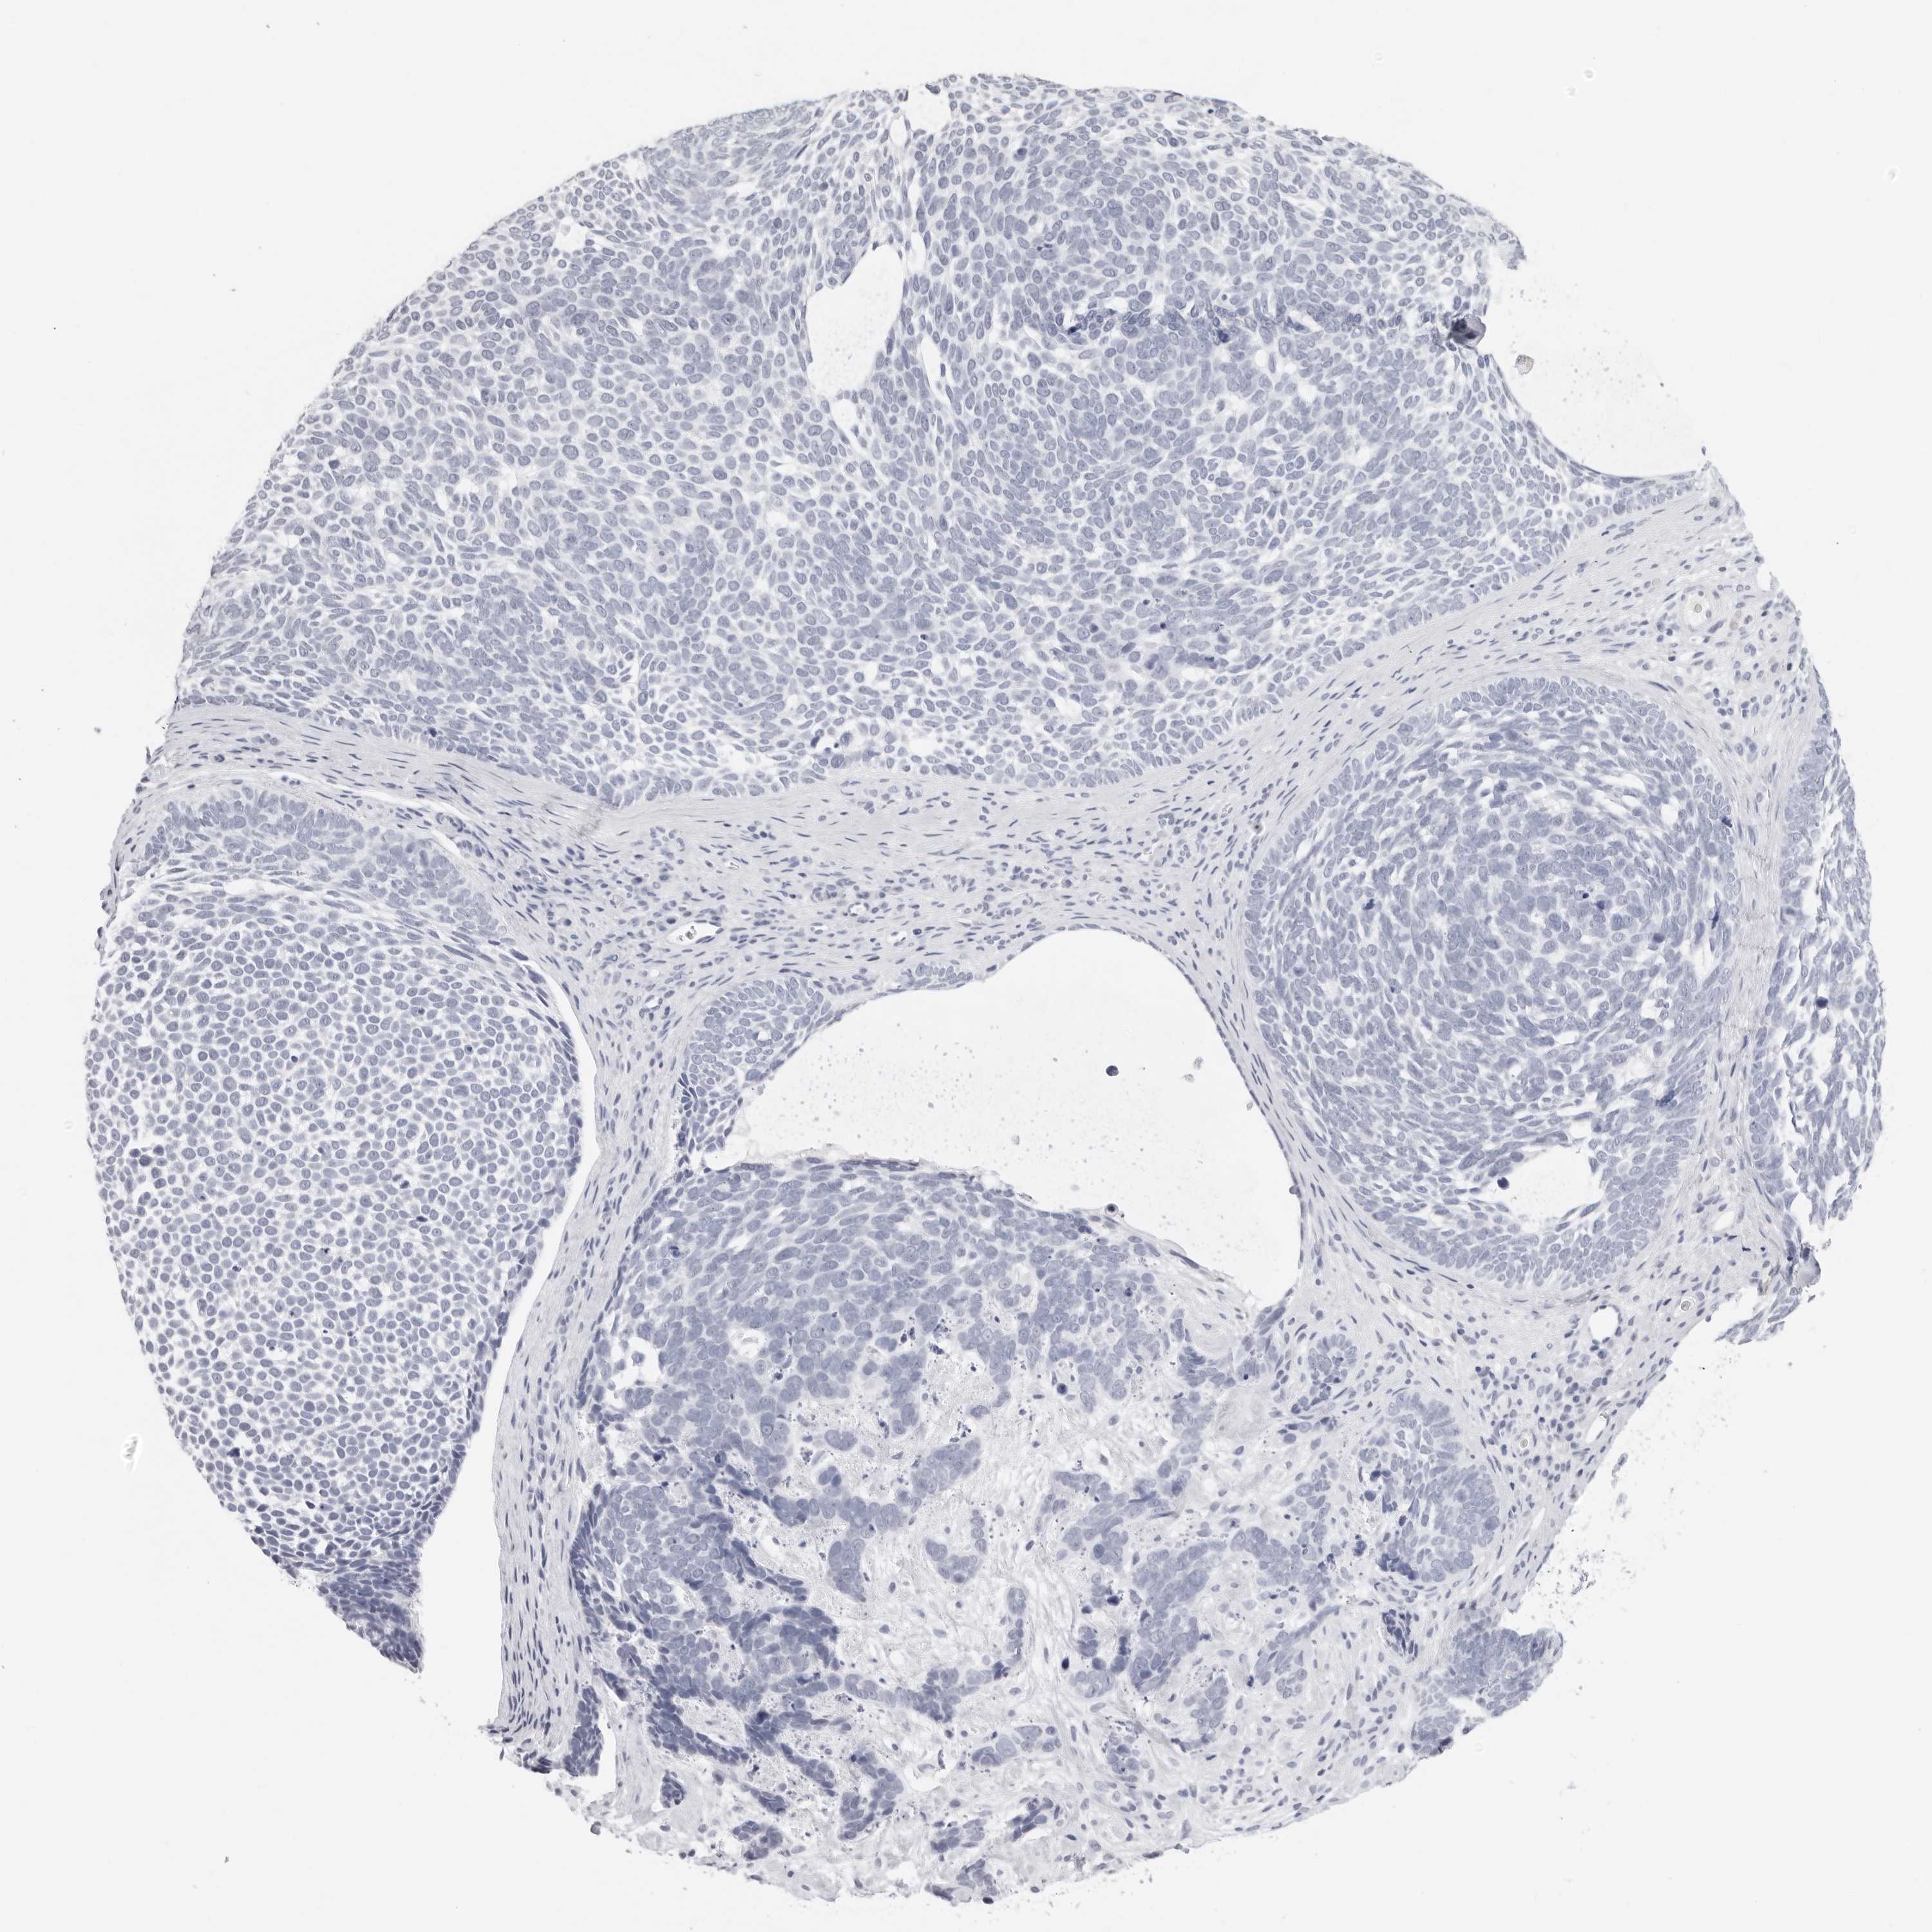

CANCER SKIN CANCER Show tissue menu

Basal cell and squamous cell cancer

SKIN CANCER - Protein expressioni

A mouse-over function shows sample information and annotation data. Click on an image to view it in a full screen mode. Samples can be filtered based on level of antibody staining by selecting one or several of the following categories: high, medium, low and not detected. The assay and annotation is described here.

Each image is clickable and will lead to virtual microscopy that enables deeper exploration of all samples and also displays staining intensity scores, fraction scores and subcellular localization as well as patient and tissue information for each sample.

Antibody HPA026443

Basal cell carcinoma

Squamous cell carcinoma, NOS